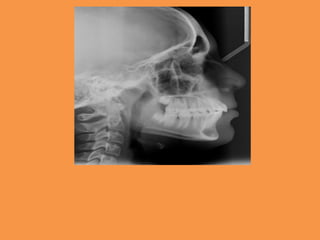

Fig.1a-b Intra-oral photographs

Fig.2 Panoramic radiograph showing

impacted maxillary central

incisor and mesiodens in region of 21